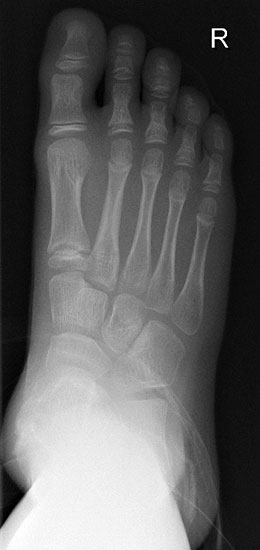

Konventionelle Röntgenaufnahmen bleiben in der bildgebenden Diagnostik von Knochen­tumoren das wichtigste diagnostische Werkzeug. Zahlreiche Informationen können hierdurch einfach, kostengünstig und im Vergleich zu einigen alternativen Untersuchungsmethoden strahlungsarm eingeholt werden. Die in der konventionellen Diagnostik eruierbaren und zur weiteren Abklärung erforderlichen Informationen beinhalten Befunde zu Topographie der Läsion (Lokalisation im Fußskelett und im individuellen Knochenbereich), Begrenzungen der Knochenläsion, Art der Osteodestruktion und Periostreaktion, radiologische Erscheinung der Tumormatrix (Zusammensetzung des Tumorgewebes, z.B. dystrophe Verkalkungen) sowie Verhalten und Ausmaß der Weichteilbeteiligung. Dabei sollte der abzubildende Knochen immer einschließlich der benachbarten Strukturen und angrenzenden Gelenke dargestellt werden. Die Röntgenaufnahmen sind stets in mind. zwei Ebenen anzufertigen. In Abhängig­keit der Beschwerden sind belastete Aufnahmen im Stehen anzustreben um zusätzliche Aussagen zur Statik zu erlangen. Die Schrägaufnahme des Fußes stellt eine sinnvolle Ergänzung zu den Standardeinstellungen (dorsoplantar/a.p. und streng lateral) dar um die Knochen des Fußskeletts möglichst überlagerungsfrei darstellen zu können. Ziel- und Spezialaufnahmen können bei Bedarf zusätzlich durchgeführt werden.

Nach Lodwick können die auf dem konventionellen Röntgenbild sichtbaren Destruktions­muster in drei Hauptgruppen unterteilt werden: Rein geographische (umschriebene) Knochendestruktion, die eine langsame Wachs­tums­geschwindigkeit widerspiegelt (Grad 1), gemischt geographisch/ mottenfraßartige Knochendestruktion mit permeativer Komponente, die eine intermediäre bis hohe Wachstums­geschwindigkeit anzeigt (Grad 2) und rein mottenfraßartige oder permeative Destruktion, die Zeichen einer sehr schnellen Wachstums­geschwindigkeit ist (Grad 3). Die erste Hauptgruppe unterteilt sich wiederum in sklerotisch deutlich abgrenzbare Läsionen (1a, sehr langsam wachsend), Osteolysen meist ohne Sklerosesaum und >1cm (1b, langsam wachsend) und weiterhin geographisch, also ausreichend gut abgrenzbare Osteolysen, welche obligat eine vollständige Kompaktapene­tration aufweisen (1c, mittlere Wachstumsgeschwindigkeit) (Tab. 1, Abb. 7). Sobald eine Grad 1c Knochenläsion nach Lodwick vorliegt, müssen weitere diagnostische Schritte diskutiert werden. Diese beinhalten üblicherweise eine MR-tomographische Untersuchung, gefolgt von einer Biopsie.